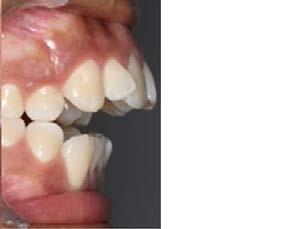

Caso clínico: paciente femenino de 19 años, patrón dolicofacial, perfil convexo, clase II esqueletal debido a una retrusión mandibular, mordida abierta anterior esqueletal, clase II molar, clase canina no establecida por mordida abierta, apiñamiento severo superior e inferior y deglución atípica.

Resultados: obtención de una clase canina I y clase molar II funcional, se corrigieron las sobremordidas horizontal y vertical, y se logró la coincidencia de líneas medias facial y dental. El manejo de la mordida abierta anterior se llevó a cabo por medio de la corrección del hábito de deglución atípica con la ayuda de spikes de resina, elásticos intermaxilares y arcos utility, y se obtuvieron buenos resultados estéticos, dentales y funcionales.